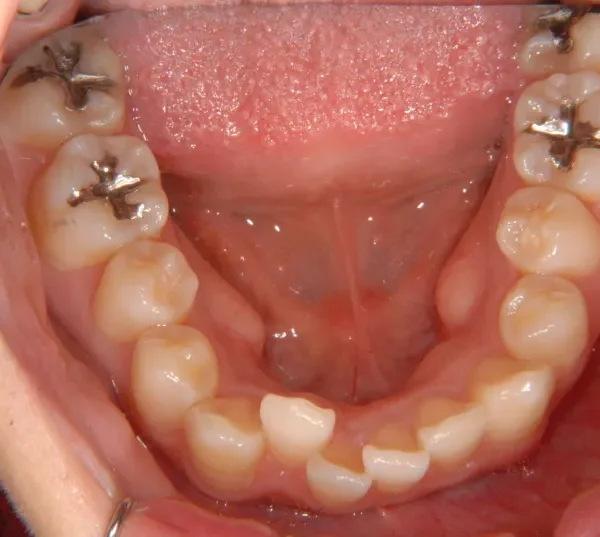

奥歯が内側と前方にかたむき上下の歯がガタガタに生えています。

90度ねじれた歯もあります。前歯も出っ歯になっています。

歯は抜かず、歯科矯正用アンカースクリューを用いて治療しました。

初診時